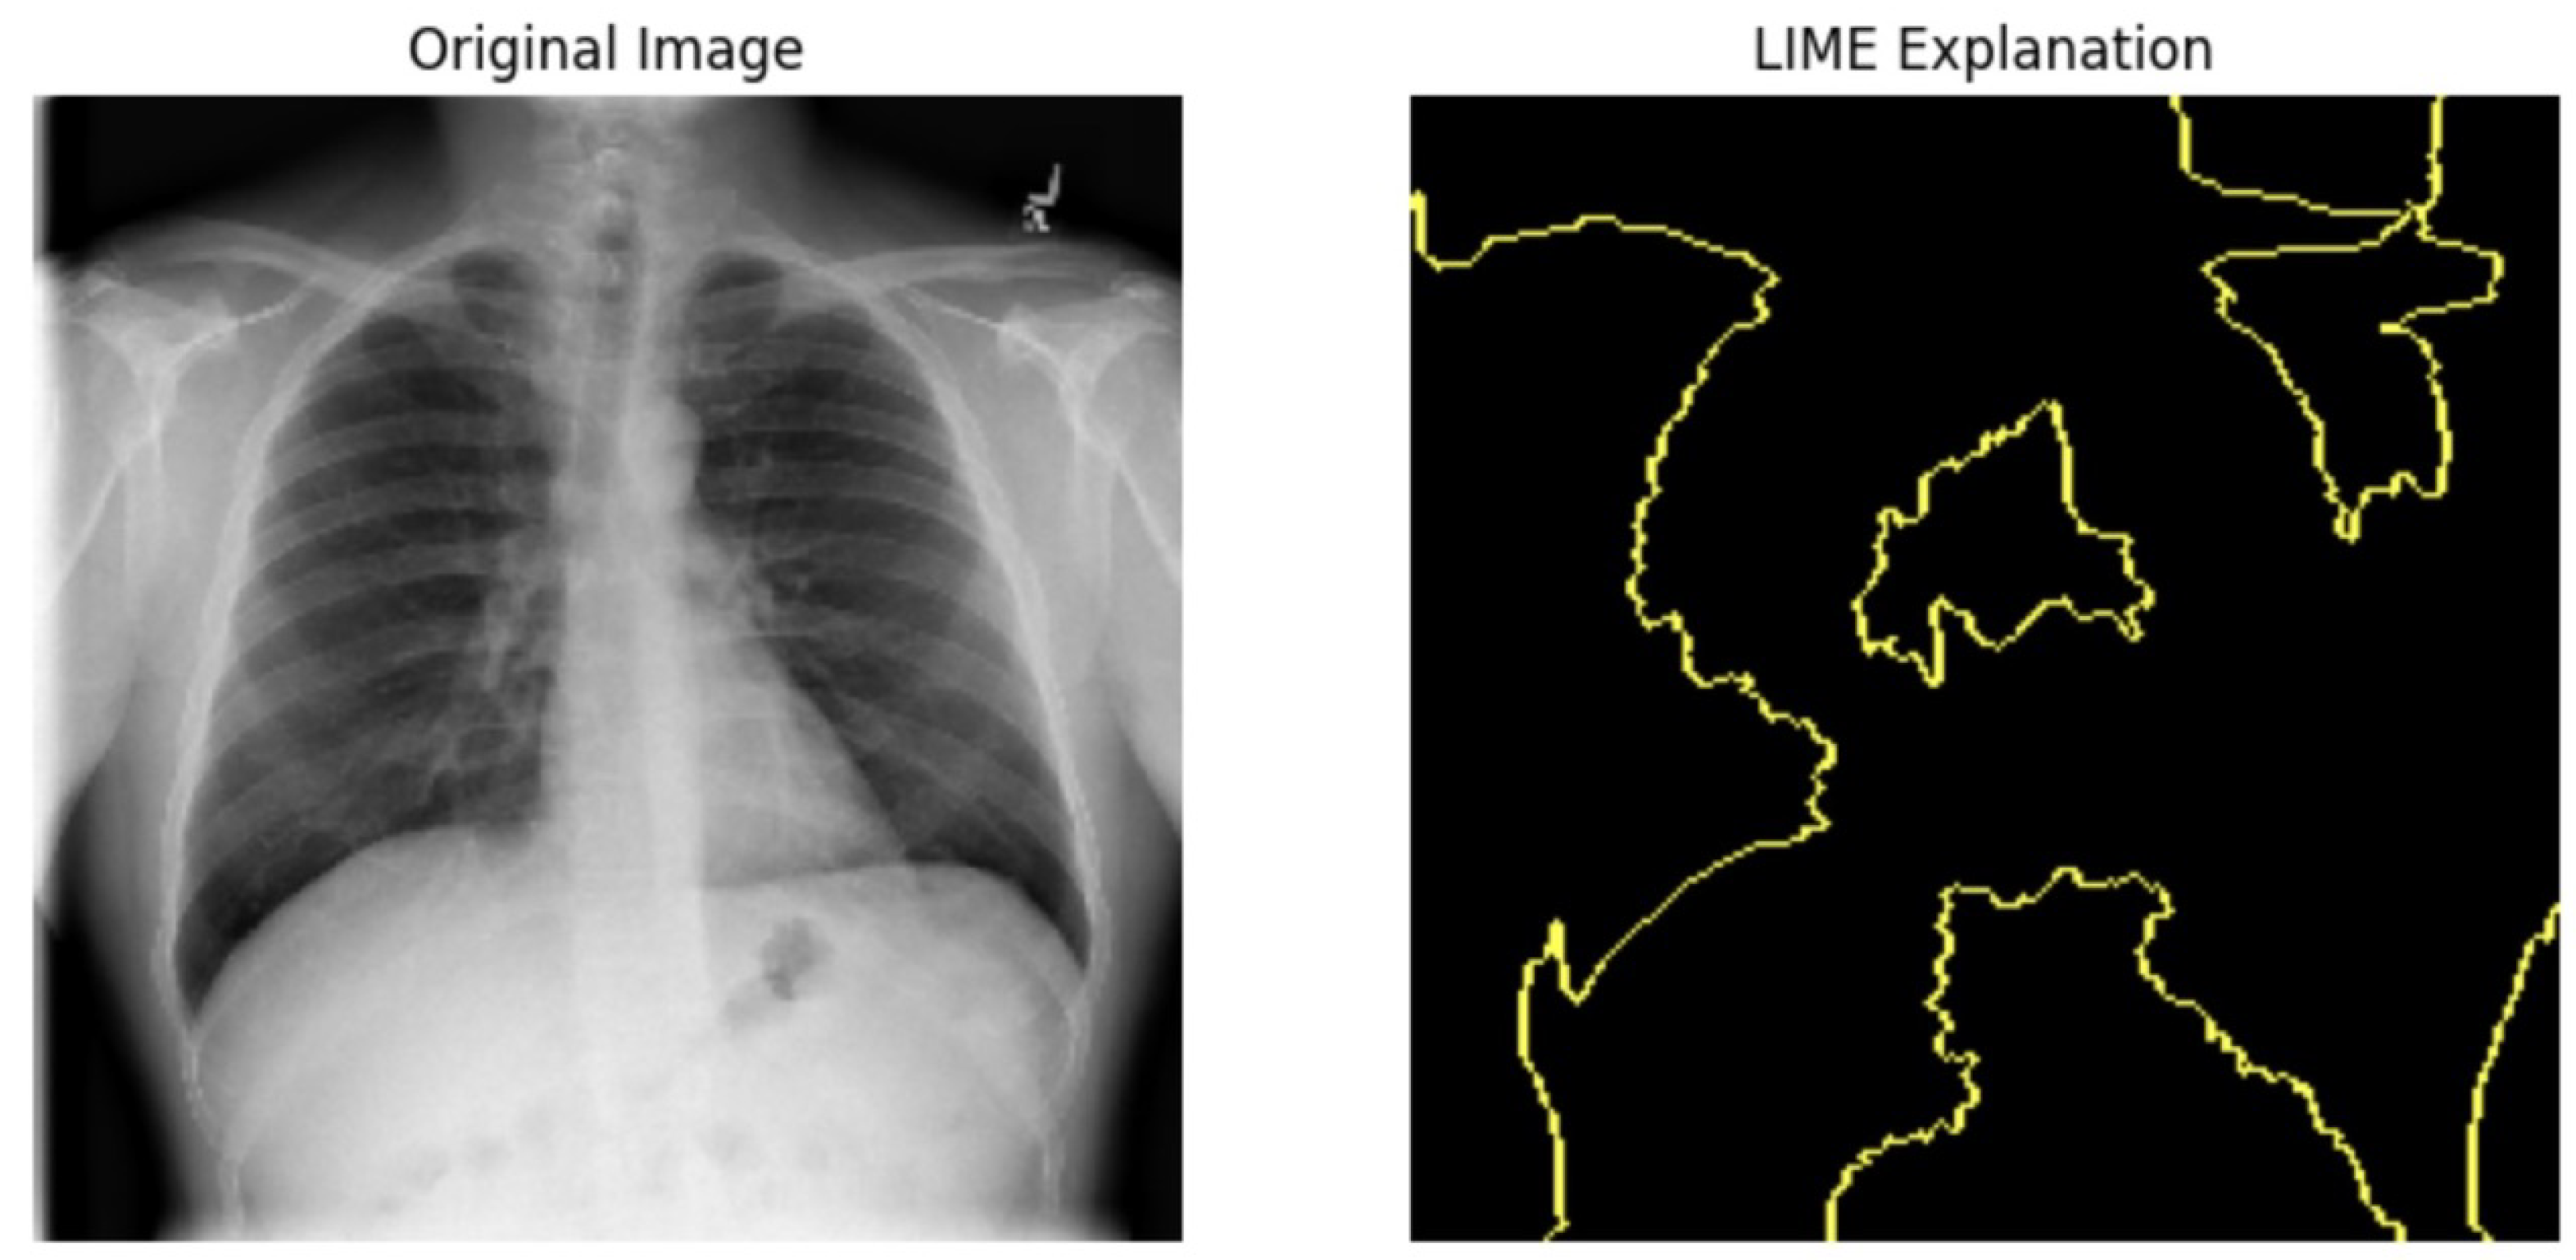

5.4.1. Local Interpretable Model-Agnostic Explanations for Clinical Validation

We applied scientific analysis on a random 7 sample, which was provided by the clinical specialist. The LIME Analysis for Image Data (a), (b), (c), (d), (e), and (f) is in Figure 22, Figure 23, Figure 24, Figure 25, Figure 26 and Figure 27. There are two parts of LIME analysis from the provided chest X-ray images to detect the disease area. Original Image and LIME explanation;

• Original Image: The patient’s thoracic cavity. It displays the typical anatomical structures of the chest, including the lungs, ribs, and heart.

• LIME Explanation: The result of applying LIME to the chest X-ray image. The yellow boundaries indicate the regions of the image that were most influential in the model’s decision-making process when determining whether the image indicated a particular condition. In this context, these regions are the parts of the X-ray that the AI model considered most important for making its diagnostic prediction.

The analysis very useful for clinicians to understand the model’s behavior and ensure that it aligns with medical expertise. The use of LIME helps in making the AI model’s interpretability decisions more transparent and interpretable. It allows medical professionals to verify whether the AI’s focus areas correspond to clinically significant regions. It also enhanced diagnostic capability of understanding which parts of the images in the AI model in refining the model further and ensures that it makes accurate and reliable predictions. This is particularly crucial in medical diagnostics where interpretability and accuracy are paramount.

Figure 24. LIME Analysis for Image Data (c) on original image to LIME explanation.